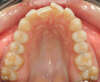

Des petits alignements dentaires (Fig. 2)

Figure 2 — Correction des malpositions incisives supérieure